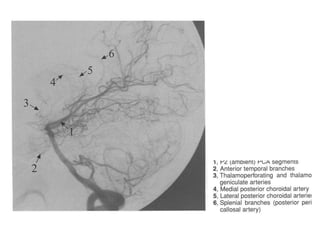

Segmentação da ACP

• P1(pré-comunicante): estende-se da bifurcação da AB até a

junção da AComP. Nos casos de padrão não fetal, P1 é mais

calibroso que a AcomP.

• Os ramos relativamente constantes de P1 são:

• Artéria talamoperfurantes, que entra no encéfalo pela

substância perfurada posterior.

• Artéria coroidea póstero-medial ( dirige para III ventrículo e VL)

• Ramo para a placa colicular.

• Ramos para o pedúnculo cerebral e segmento do mesencéfalo.